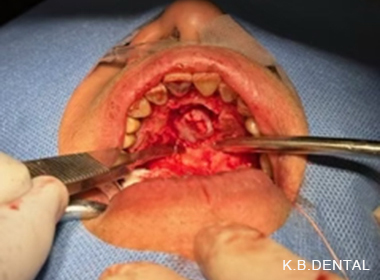

顎骨腫瘍摘出+埋伏歯抜歯 症例2(口腔外からの埋伏抜歯+顎骨腫瘍摘出術)

様々な問題で口腔内からの処置が難しい場合には口腔外から行うこともあります。